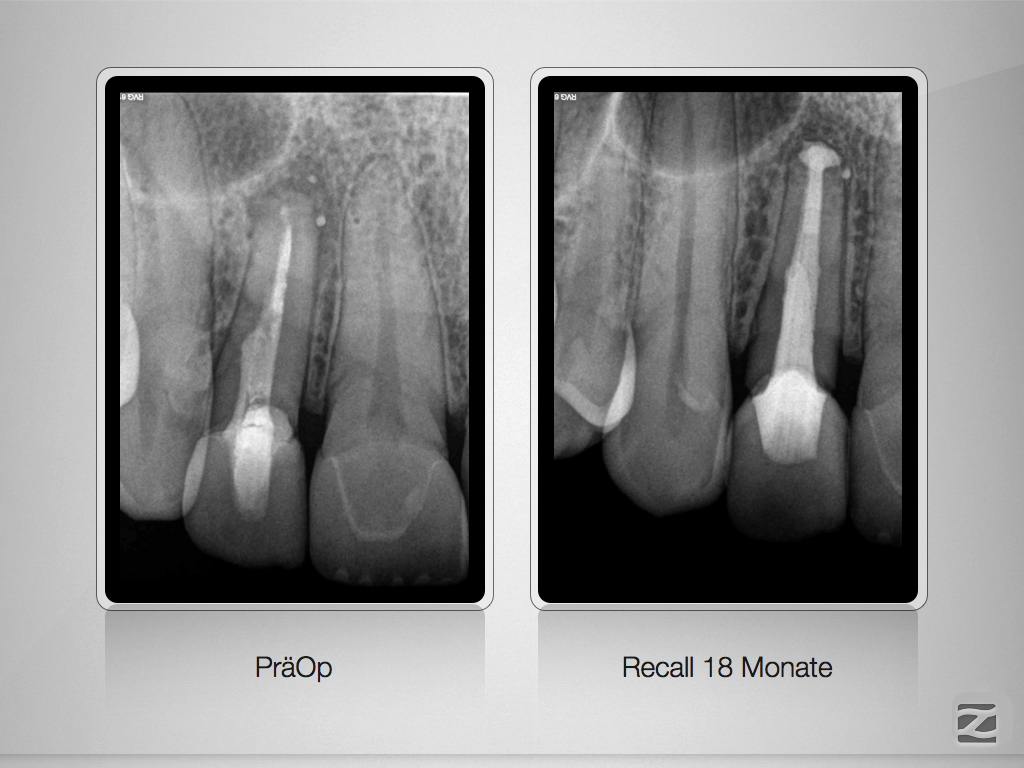

12D.007

Kurioses Leakage